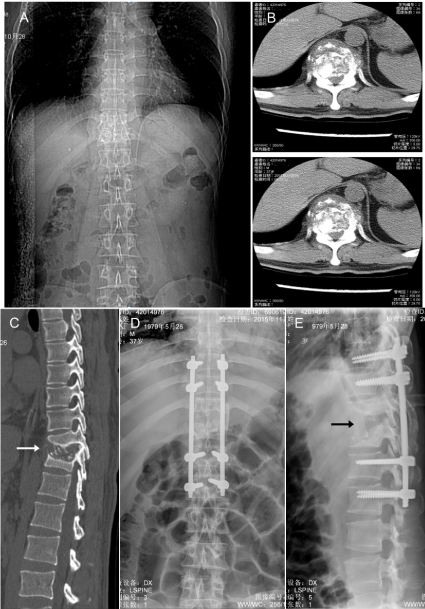

Figure 1. X-ray images of severe vertebral destruction and abscess formation. (A). A representative of preoperative X-ray photograph indicates the location of damaged thoracic spine; (B). A close-up view of destruction in a preoperative CT image; (C). A lateral view of the preoperative damage in CT (arrow); (D, E) X-ray images show in positive and lateral position of the pedicle screws for fixed spine after operation. All images were taken from the same patient.